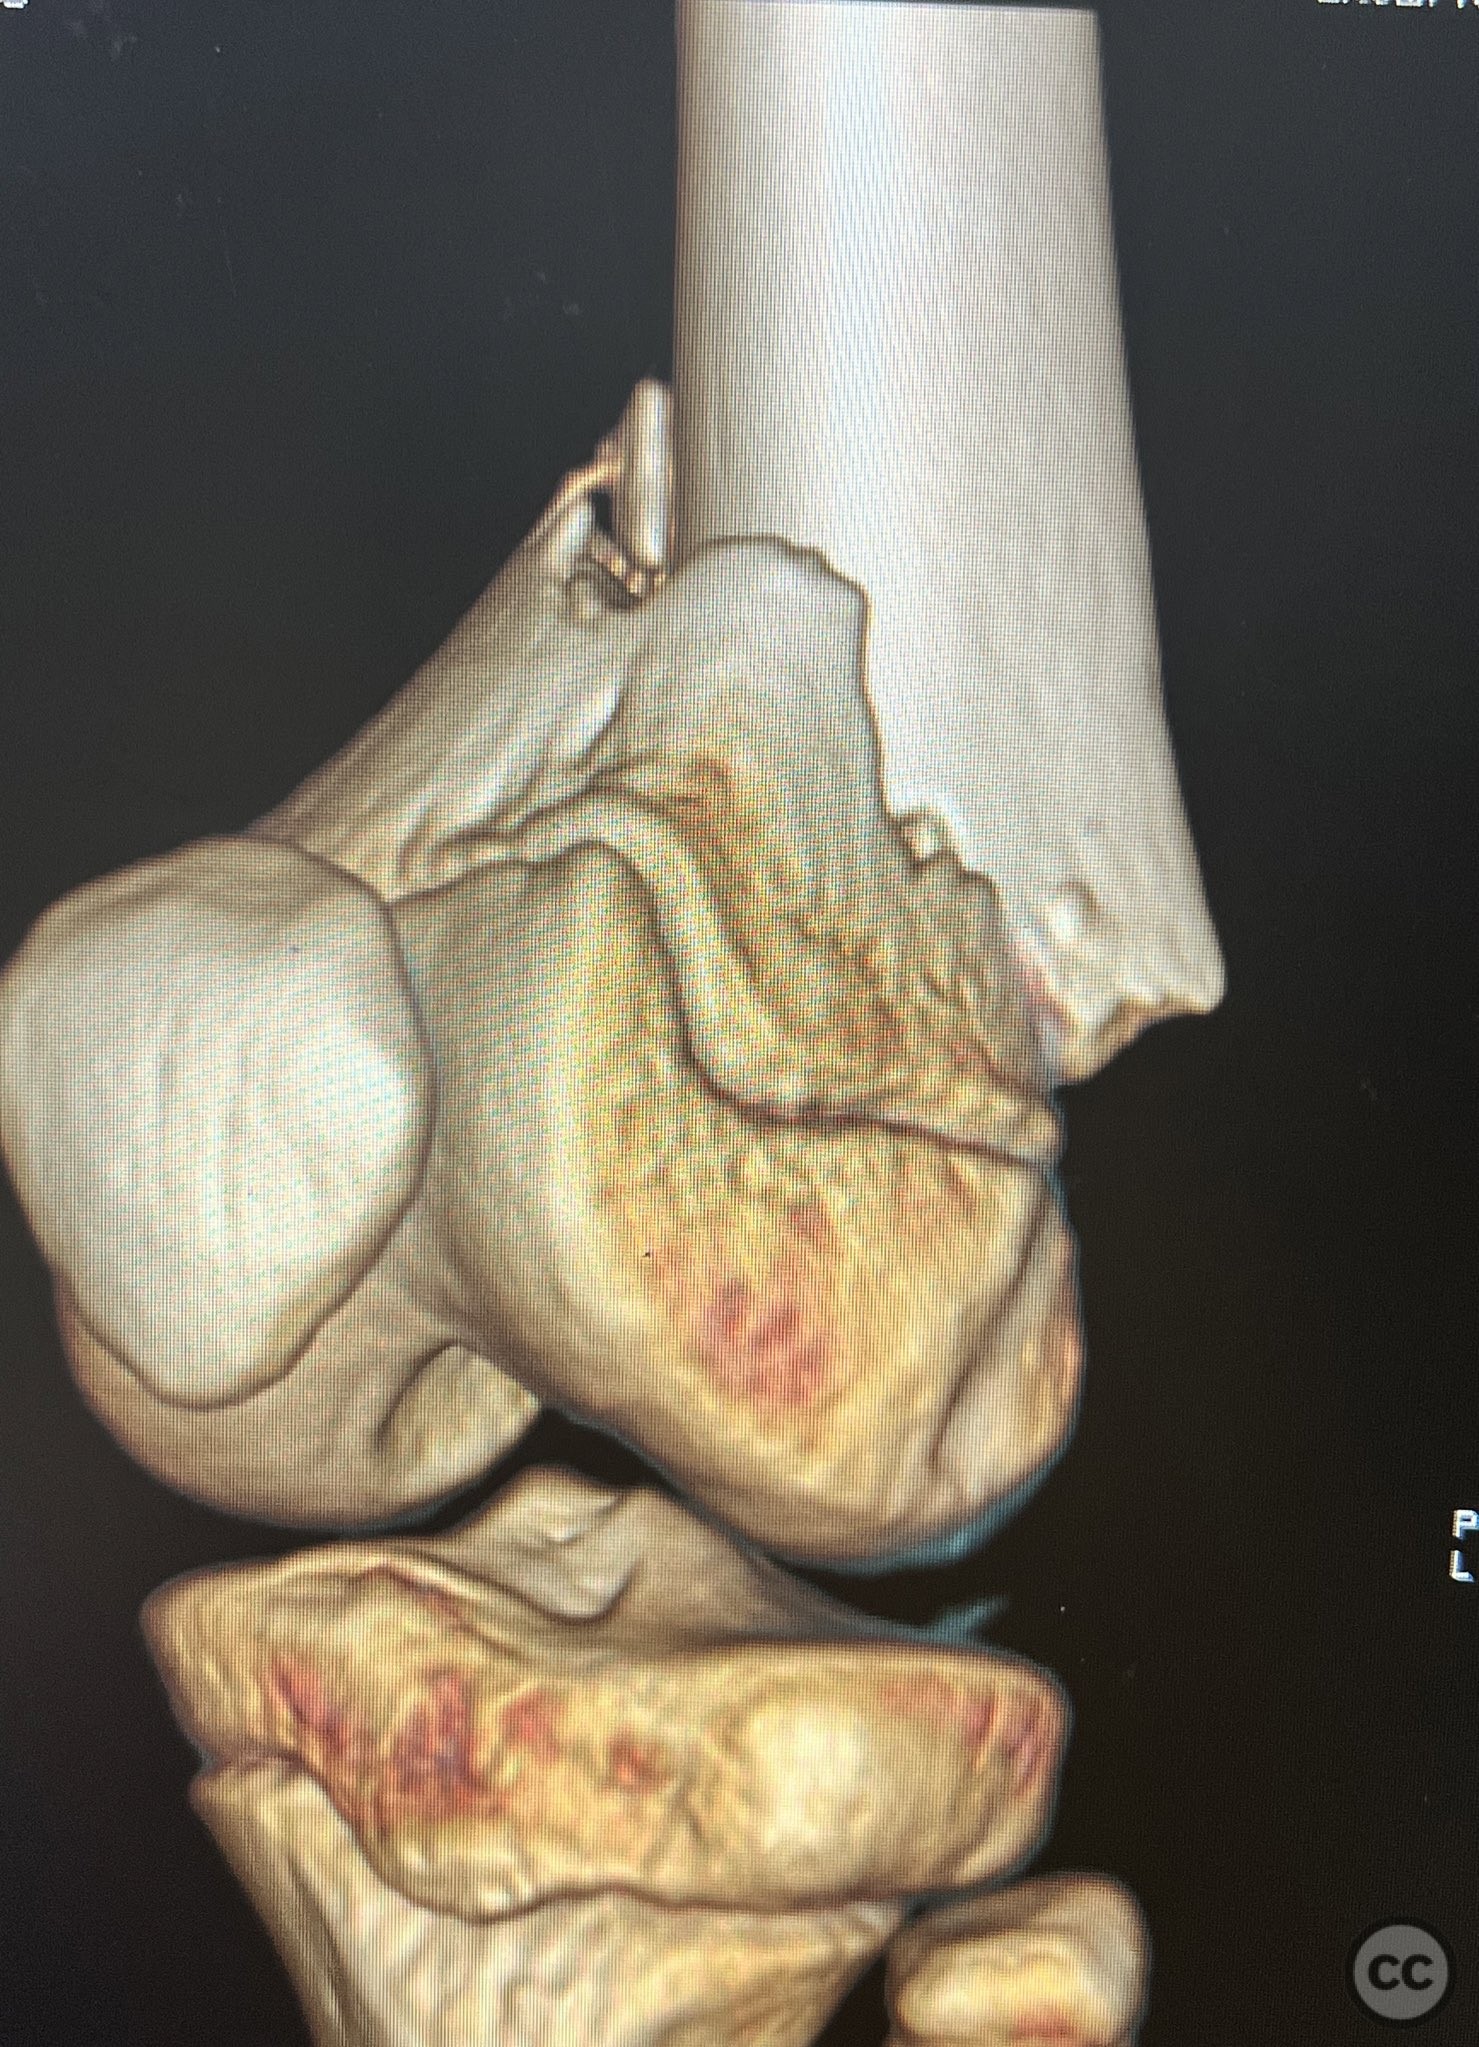

Supracondylar femur fracture in an 11yo

Schleswig Holstein, Germany

Paediatric - PCCF